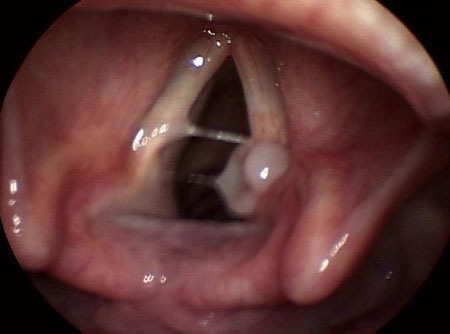

A paralisia unilateral das pregas vocais é comumente idiopática ou secundária à disfunção de nervos.[16][Figure caption and citation for the preceding image starts]: Paralisia da prega vocal esquerdaDo acervo da University of Wisconsin School of Medicine and Public Health [Citation ends].

Outras causas incluem trauma cirúrgico (tireoidectomia, fusão cervical anterior, reparo de aneurisma aórtico torácico, esofagectomia, cirurgia da base do crânio) e cateterização venosa central; tumores malignos ou benignos no cérebro, na base do crânio, na tireoide, no timo e no esôfago; massas no espaço parafaríngeo e neuromas vagais e doença neurológica (acidente vascular cerebral [AVC], esclerose lateral amiotrófica, síndrome pós-poliomielite, doença de Charcot-Marie-Tooth, paralisia bulbar).[16][17]

A paralisia bilateral das pregas vocais apresenta etiologias similares ao seu correlato unilateral, mas é significativamente mais rara.[18][19] As causas comuns incluem tireoidectomia, doenças congênitas (malformação de Chiari), lesões no tronco encefálico, intubação prolongada, fibrose por radioterapia da cabeça e pescoço e doenças granulomatosas (tuberculose [TB], sarcoidose, amiloidose).